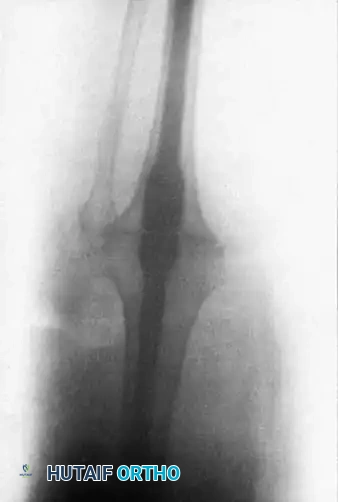

Bone Resection and Preparation

- Tibial Preparation: Using an oscillating power saw with continuous saline irrigation to prevent thermal necrosis, the superior surface of the tibia is cut exactly transverse to the long axis of the bone. A wafer of cartilage and subchondral bone (approximately 1 cm thick) is removed.

- Femoral Preparation: An appropriately sized segment of the distal femur is resected to ensure that the raw bony surfaces appose perfectly when the knee is held in the desired alignment (0-15° flexion, 5-8° valgus). Standard TKA cutting blocks and intramedullary alignment guides are highly useful for making these precise cuts.

Surgical Warning: Bone Preservation in Salvage Cases

If arthrodesis is being performed after a failed TKA, the surgeon must avoid removing additional bone from the femur and tibia. Instead, thoroughly debride the sclerotic surfaces with a high-speed burr and attempt to interdigitate the irregular metaphyseal surfaces to maximize contact area without further shortening the limb.